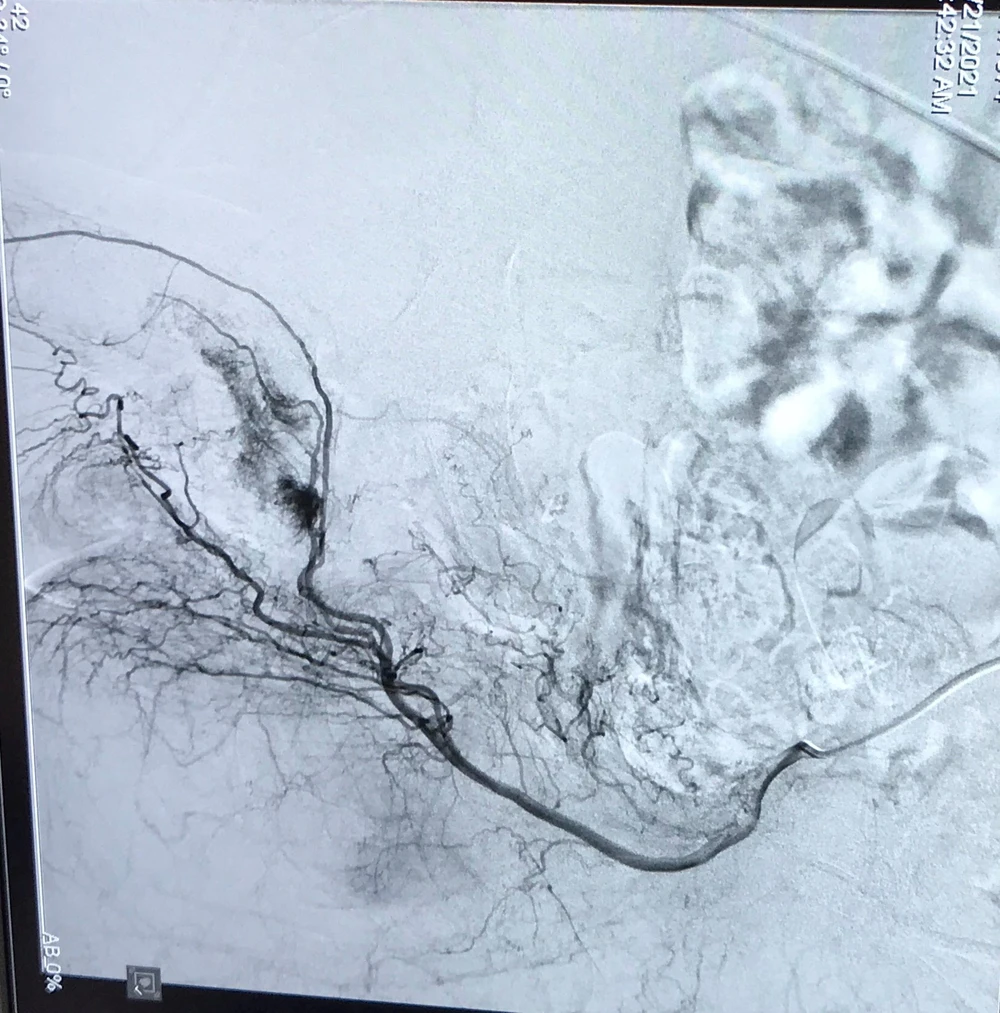

Ảnh chụp MRI của bệnh nhân tại BV Đại học Y  Hà Nội

Trước tình hình như vậy, các bác sĩ Nam học đã hội chẩn với các bác sĩ điện quang can thiệp mạch, quyết định tiến hành chụp mạch dương vật và nút lỗ rò động mạch hang.